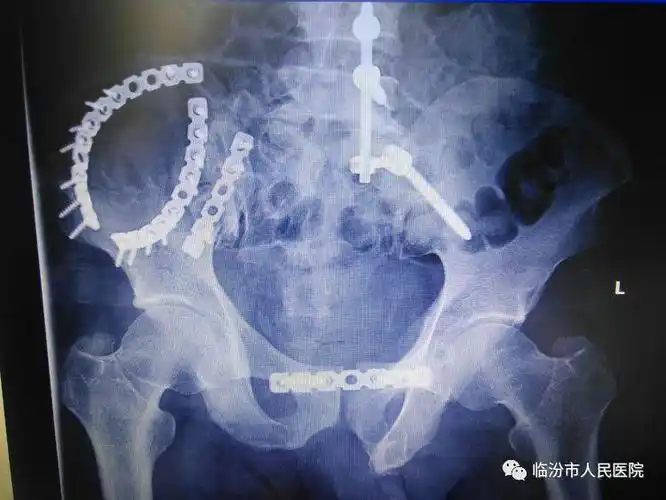

腰骶髂骨脊柱椎弓根钉棒内固定系统治疗骨盆骨折的临床应用